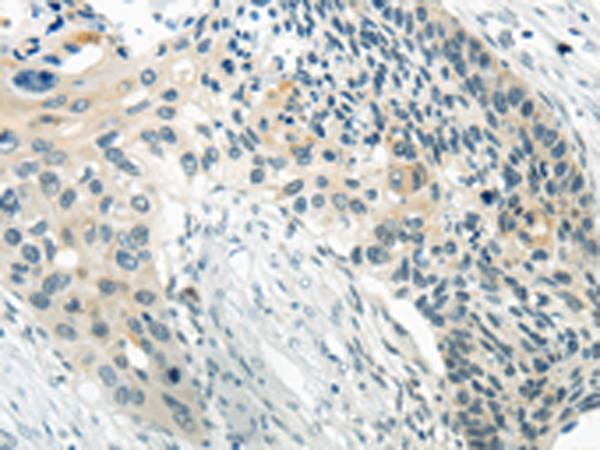

分类: 科研抗体货号: P12437别名: AIRAP应用: WB,IHC反应种属: Human